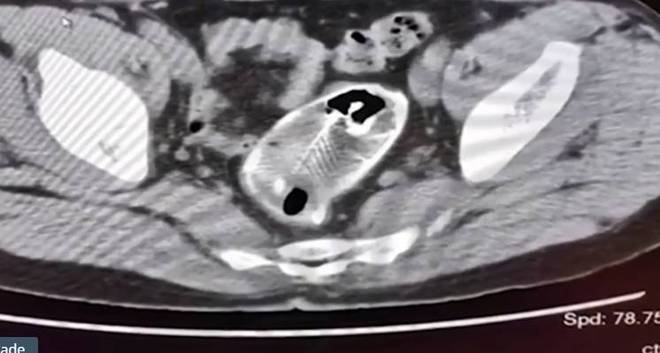

Ele então fez uma série de tomografias e raios X, que encontraram a fonte do problema

Se tratava de um peixe de água doce...

... alocado no reto do homem

Depois que o peixe, uma tilápia de Moçambique, foi encontrado, os médicos perceberam que era grande demais para ser removido por uma endoscopia de emergência

Eles então descobriram que as barbatanas espinhosas da criatura haviam causado rupturas no intestino grosso